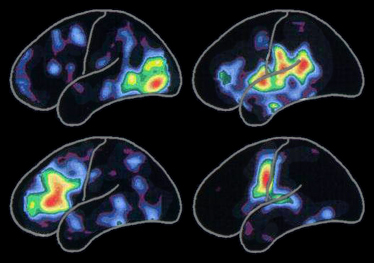

Hình ảnh phân tích chụp cắt lớp hình ảnh phát xạ hạt nhân (PET) trên bán cầu não trái thể hiện các vùng đặc trưng của hoạt động não gắn liền với:

Hoạt động nhiều nhất ở các vùng màu đỏ và sau đó giảm dần đến các màu khác trong dải sắc cầu vồng và lần đến xanh - tím.

Các vùng hoạt động đặc trưng biến đổi suốt cả cuộc đời khi chúng ta gặp gỡ những người mới, có những kinh nghiệm mới và tiếp thu các kỹ năng mới. Các vùng cũng biến đổi khi mắc bệnh Alzheimer hay bệnh lý có liên quan phá hủy tế bào thần kinh và các liên kết của chúng với các tế bào khác.